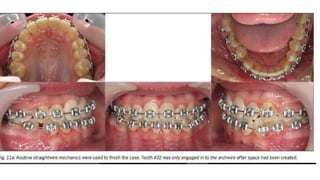

• 77.

Treatment sequencing The patient'smaxillary arch was bonded to include all teeth except unerupted canines. After three months, adequate space was created to bond the erupted canines. After six months of maxillary-only appliances, no significant mandibular growth had taken place .

• 78.

Because of this,bonding a lower sectional appliance from molar to canine on the Class III side was done . A 0.014 NiTi wire was used and an active tieback placed before dental extraction.

This complex, asymmetricClass III case has treated out quite well and efficiently. The use of the active tieback to close the extraction space provided all the anchorage necessary in this maximum anchorage situation. Why aren't all complex orthodontic cases requiring extraction being treated this way and completed in 15-18 months? After all, it's extremely simple to do, the molars are great anchorage and best of all, the RAP is free turbocharging for space closure.